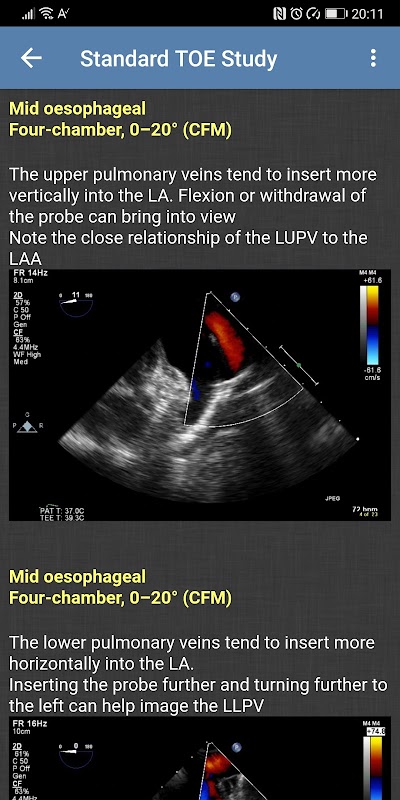

- Standardowe badanie TOE